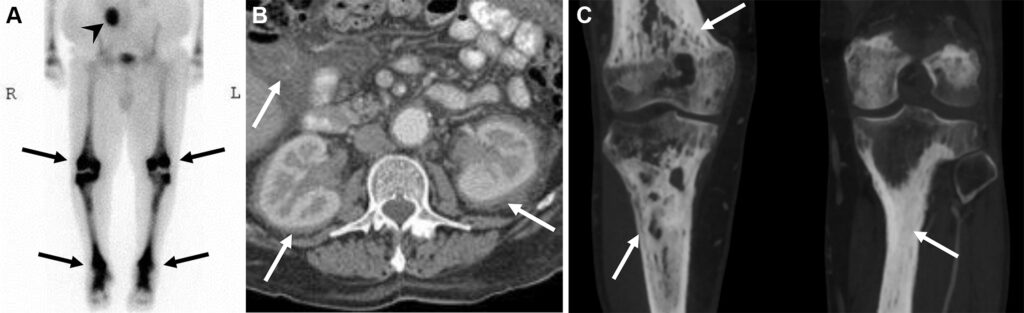

Malattia di Erdheim-Chester in un uomo di 47 anni con dolore osseo aspecifico.

La scintigrafia ossea whole-body evidenzia un’intensa ipercaptazione simmetrica e confluente a carico delle ossa lunghe (in particolare distretto dia-metafisario ed epifisario di ginocchia e caviglie). Come reperto incidentale, si osserva un ristagno di tracciante nel rene destro, indice di ostruzione delle vie urinarie.

La TC conferma una marcata osteosclerosi nelle medesime sedi ipercaptanti e la presenza di una massa tissutale infiltrante che avvolge simmetricamente i reni (aspetto a “cercine” o hairy kidney) e infiltra il mesentere. Questa fibrosi retroperitoneale spiega l’ostruzione dell’efflusso renale destro rilevata in scintigrafia.

La malattia di Erdheim-Chester è una rara istiocitosi non-Langerhans caratterizzata da una proliferazione sistemica di macrofagi. Il pattern di osteosclerosi simmetrica dia-metafisaria bilaterale delle ossa lunghe, associato all’infiltrazione perirenale, è considerato un quadro radiologico quasi patognomonico per questa patologia.